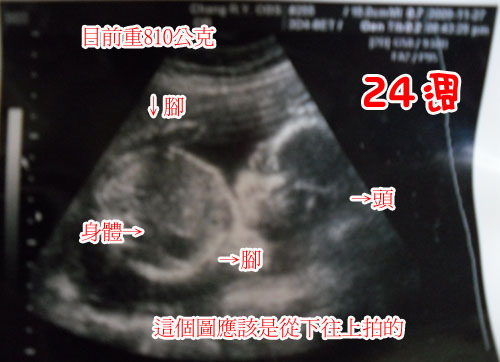

*My Baby 希:胎兒篇